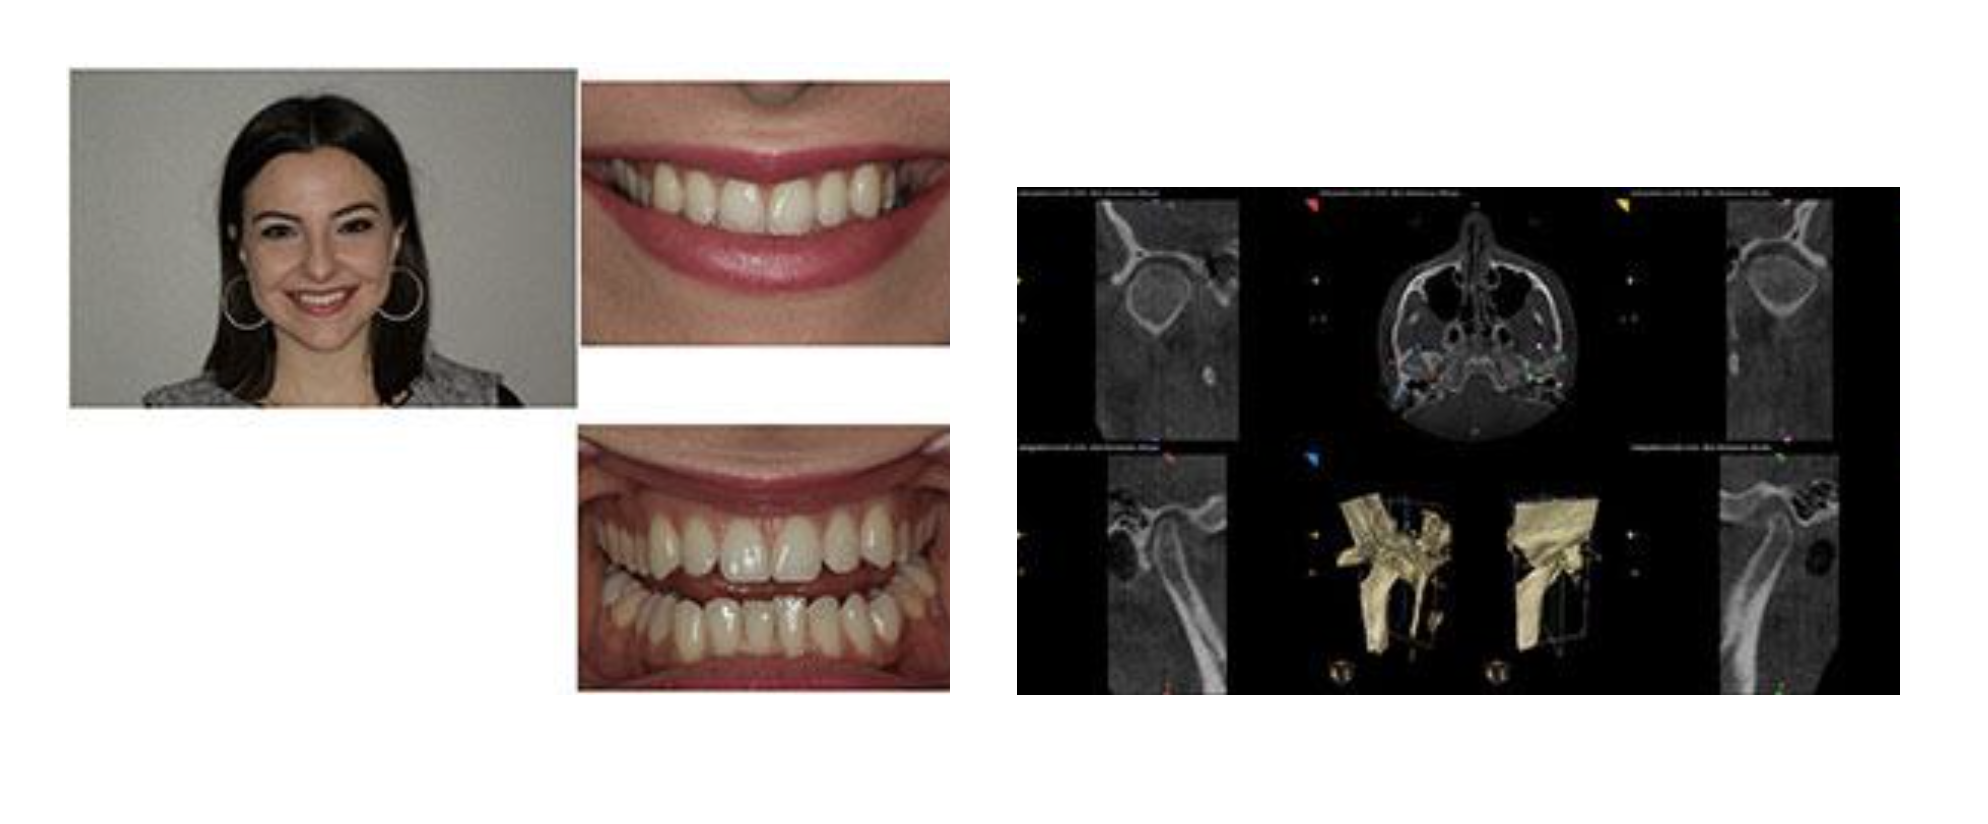

This healthy 24-year-old female patient presented to me for treatment of her potential TMJ disorder (Figure 1). Despite her healthy dentition, attractive facial appearance, and age, she was suffering from the following:

Our diagnostic workup included a comprehensive exam, full-mouth series of x-rays, 3-D CBCT, diagnostic photographs, diagnostic impressions, and a very detailed neuromuscular questionnaire. Based on the patient’s symptoms, lower midline shifted to the left, and depressed curve of spee, we suspected a torqued mandibular position compressing the condyles and resulting in muscular distress.

Figure 1 (left). A healthy 24-year-old female presented with severe TMJ symptoms. Figure 2 (right). The 3-D cone beam view revealed the posteriorized position of both condyles.

This posteriorized position of both condyles was confirmed and evident in the 3-D cone beam view (Figure 2). There was also significant beaking of the left condyle that demonstrated the bony changes it has undergone due to its destructive position and dysfunction.